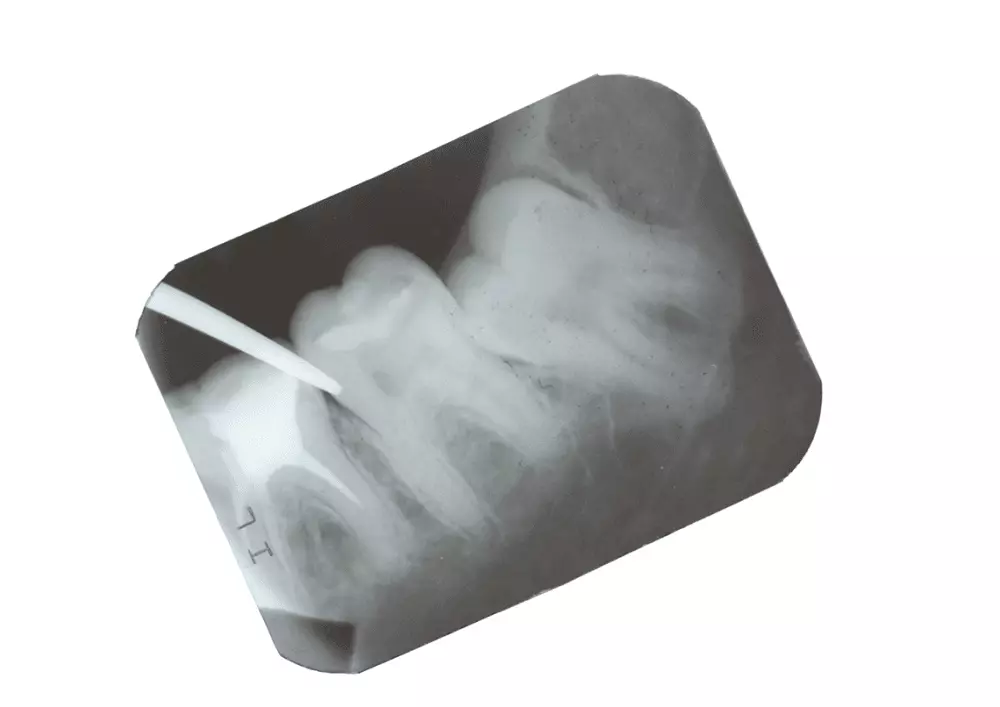

Dr n. med. Marcin Aluchna w swoim artykule opisuje zastosowanie skalera w stomatologii na przykładzie urządzenia Newtron. Działa on na zasadzie ruchu drgającego końcówki (minimum 28 kHz). Technologii Cruise Control umożliwia kontrolę generatora w czasie rzeczywistym. Szczegóły w najnowszym numerze.